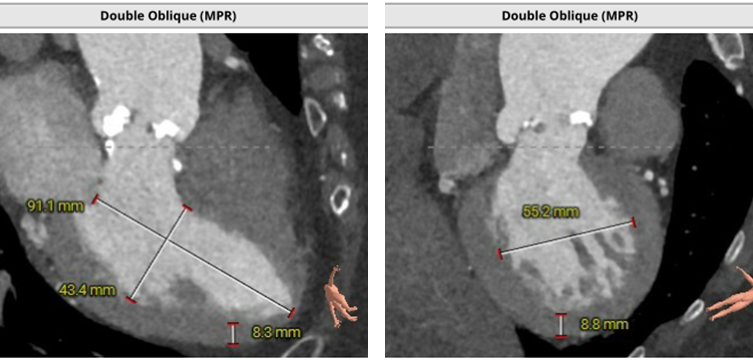

术前CT评估:

CT测量小结:

主动脉瓣为type -I 型二叶瓣,右无瓣叶嵴部融合伴有钙化并向窦部延伸16.0mm,瓣环平面可见钙化斑块向左室流出道延伸约12.3mm,瓣叶极重度钙化,中重度增厚;左冠窦较右无冠窦略偏大,右无冠窦基本等大;右冠脉开口高度可,左冠脉开口处可见瓣叶钙化斑块;心室大小可,室壁厚度可,中重度横位心;大血管走行自然,内径可,升主动脉扩张,主动脉弓部角度可,弓部、降主、腹主、左髂总动脉可见少-中量钙化斑块。

针对瓣膜型号选择,根据主动脉瓣环面积631.1mm2折算直径28.3mm,LVOT29.0mm,按照常规标准需选择29mm PrizValve。因患者瓣叶为极重度钙化(Hu850钙化积分2322),瓣膜型号可适当downsize,应能较好在瓣膜位置锚定,也有利于减少冠脉开口阻塞风险。

综合评估后,拟采用右侧股动脉入路,25mm球囊预扩张、Balloon sizing并观察冠脉阻塞风险,左冠支架保护,26mmPrizvalve标准容量球囊扩张TAVR手术。